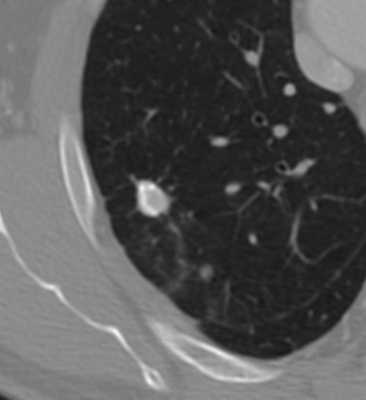

КТ-признаки туберкуломы легкого. Образование диаметром 2 см расположено в правом легком. Отличить туберкулому от рака помогает наличие глыбчатых кальцинатов (извести) в структуре образования, четкие контуры, окружающие фиброзные тяжи, а также мелкие очаги отсева вокруг.